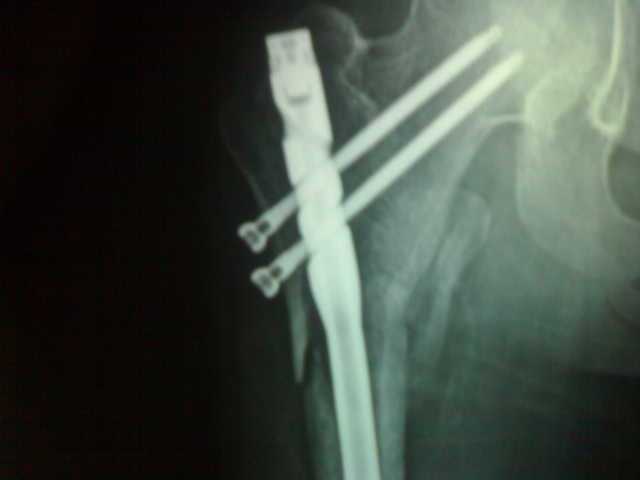

股骨头下侧右大腿粉碎性骨折

这是我骨折时的片子以及现在的片子。现在术后两个月了。内固定手术固定的这个东西请问一下现在这个情况可以负重吗。能站吗。还得多长时间才能不用拄拐恢复正常走路

首先,请无视“十三局医院”回答的内容。只要是正规医学院校出来的医生,不需要看X光片,你只要问TA股骨粉碎性骨折内固定术后2月能不能负重,TA的回答都是“不能”,这是常识。你是股骨上段粉碎性骨折,小粗隆骨折、游离,从最近这一张照片来看,骨折线是模糊了,但是还远远没有达到可以负重的程度,首先时间上就不够,这是毫无疑问的。至于需要多长时间才能正常走路,这很难说,快则半年,慢的话,1年都不行,还得重做半然狗手术。股骨骨折,尤其是粉碎性骨折,发生延迟愈合甚至骨不连的竖梅并不少见。建议跟给你做手术的医生密切联系,按时厉夕复查,看骨折愈合的情况。切记不要过早负重,否则造成骨不连,就太麻烦了。

楼主这是逆粗隆骨折吧,可不可以负重lz应该问你的主治医生,他最了解病情

骨折线已经模糊,现在起就可以下地走路,也可以不扶拐,但要注意不要扭伤,不要负重。两个月后再拍片复查骨折完全愈合后就可以负重了。